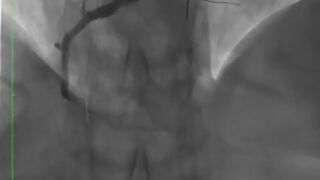

De esta manera, surgió la idea de aplicar un tratamiento pionero que consiste en liberar el fármaco en la zona de la arteria que está obstruida. Según ha indicado Sanz, "cuando el paciente tiene la arteria cerrada se le aplica un balón que se hincha durante un minuto, abriendo la arteria y liberando un fármaco" añadiendo que "una vez se realiza el proceso el balón se deshincha y se retira del cuerpo con lo que no se deja ningún tipo de metal dentro de las arterias del corazón".

Copernican es el primer ensayo clínico aleatorizado que comparará los resultados clínicos del uso de balones farmacoactivos (BFA) frente al implante de stent farmacoactivo (SFA) en pacientes que presentan infarto agudo de miocardio con elevación del segmento.